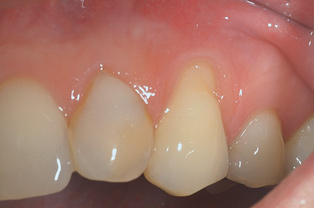

Fig 3. Tooth No. 28 had a Class V filling that failed with recurrent decay (Fig 3). A tuberosity CTG with a 1.5 mm thickness was placed, and after 1 year there was no keloid-like appearance (Fig 4).

Figure 3

Fig 4. Tooth No. 28 had a Class V filling that failed with recurrent decay (Fig 3). A tuberosity CTG with a 1.5 mm thickness was placed, and after 1 year there was no keloid-like appearance (Fig 4).

Figure 4

Class V fillings are artificial materials that tend to fail at the apical extent and have poor long-term success (Figure 3).1 Conversely, CTGs are natural and attach to the root surface and have high long-term success (Figure 4).1

Dense CT presumably is less susceptible to shrinkage than less-dense CT. One problem with denser CT may be the need for a longer amount of time to blend in with adjacent non-grafted areas. Due to density, a CT graft might never completely blend in and always demonstrate an unesthetic keloid-like appearance. Therefore, with tuberosity tissue, adjusting the tissue thickness prior to placement of the graft is highly clinically relevant. This may be why periodontists have been reluctant to use tuberosity tissue as CT. Palatal tissue has less-dense CT than tuberosity tissue and, therefore, the authors hypothesize and have observed, shrinks more. Because palatal tissue has been the predominant tissue used in CTG, clinicians have become used to the shrinkage associated with the palatal CT and may not realize the need to thin a dense CTG to prevent a keloid-like appearance. Thus, in the past when a tuberosity was used for this purpose, if it was not properly trimmed it would have frequently resulted in an unesthetic keloid-like appearance. The tuberosity CTG should be trimmed to 1 mm to 1.5 mm thick to avoid the need for a future procedure to adjust tissue thickness for esthetics (Figure 3 and Figure 4, Figure 16 and Figure 17).